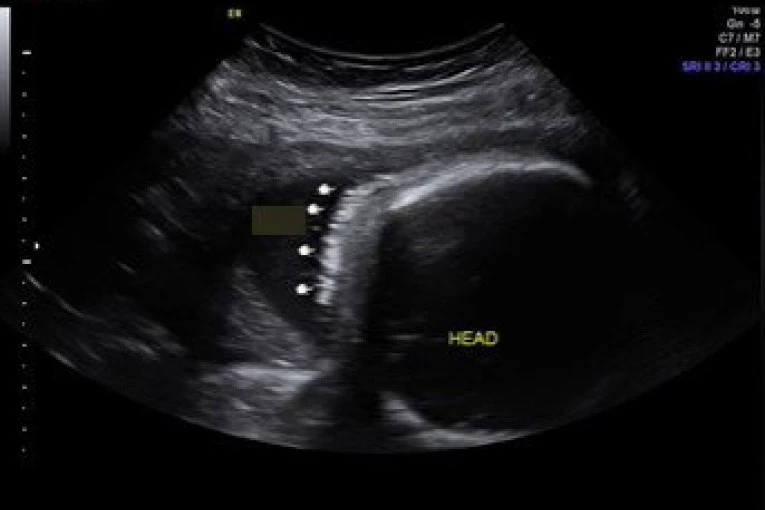

Sliku sa ultrazvuka prikazali su i u videu na TikToku. Naime, devojčica je imala kosu koja je jasno bila obeležena strelicama. Nakon ovog videa, slede slike sa porođaja. Tek tada, kosa je zaista bila primetna i mnogi su bili oduševljeni kako je lepa, gusta i crna.

Foto: Tiktok

Video je postao viralan i u rekordnom roku je skupio više od tri miliona pregleda.

"Bila sam šokirana kada sa videla dlake na ultrazvuku, nisam znala da je to moguće", "Sigurno si umirala od mučnine", "U kojoj nedelji na ultrazvuku si videla da ima kosu", "Kako je ovo moguće?", "Moja beba je imala kosu, a ja nisam imala mučnine", "Preslatka mala devojčica", pisali su joj oduševljeni ljudi ispod videa javno.